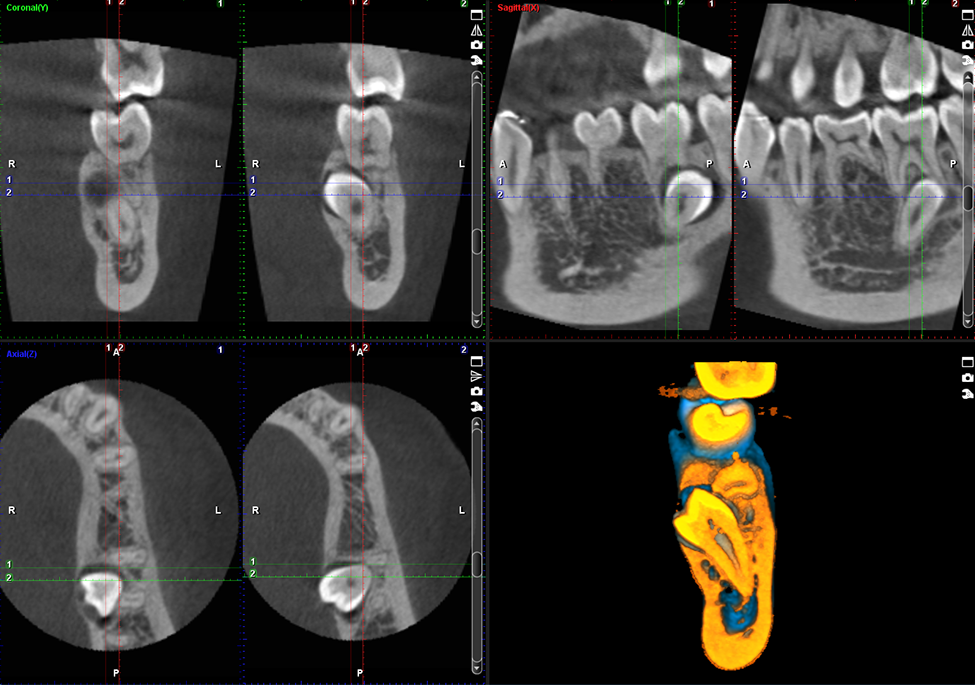

Wysokiej jakości obrazowanie endodontyczne

Jakość obrazu bez wątpienia ma ogromne znaczenie, jednak każdy obraz składa się z małych części. Oferowany przez nas tryb obrazowania endodontycznego jest idealny do wykonywania zdjęć małych szczegółów anatomicznych. Gwarantuje niezwykle wysoką rozdzielczość przy wielkości woksela wynoszącej 75 μm.

Obrazy Kliniczne Planmeca ProMax 3D Mid